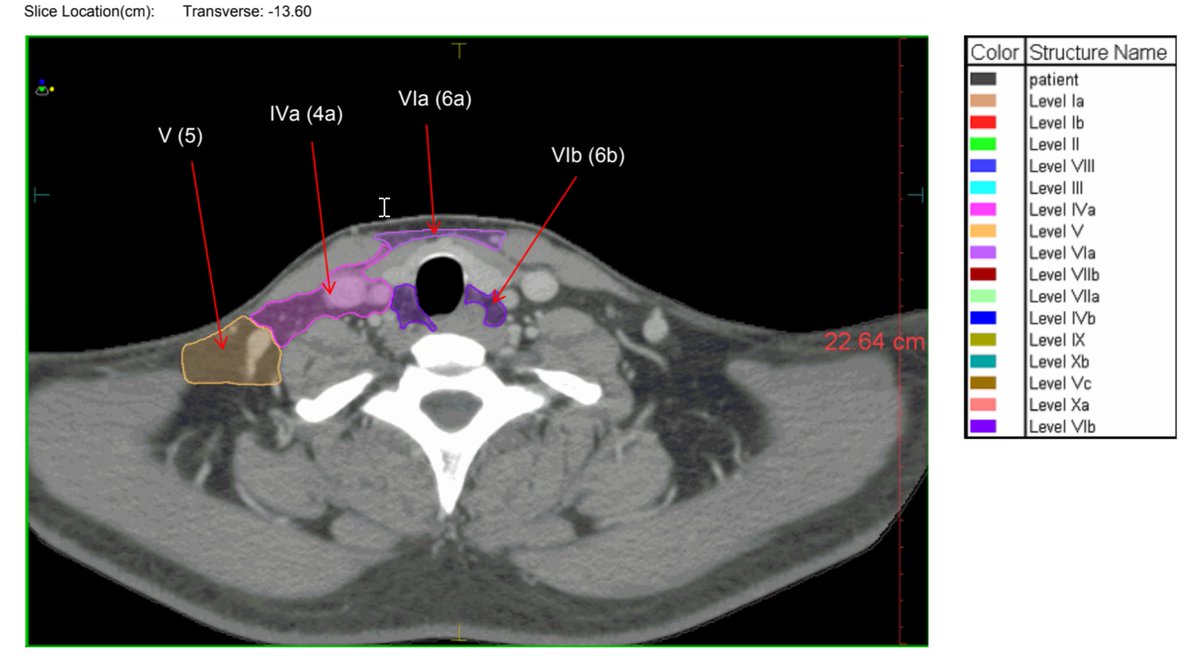

This has helped other #radonc trainees, so sharing my annotated consensus neck nodal guidelines slide deck here (Grégoire et al.)

I put labels throughout as the colors were hard to follow, making it easier to help with h&n contours

Good luck!

drive.google.com/file/d/1WE8SeB…